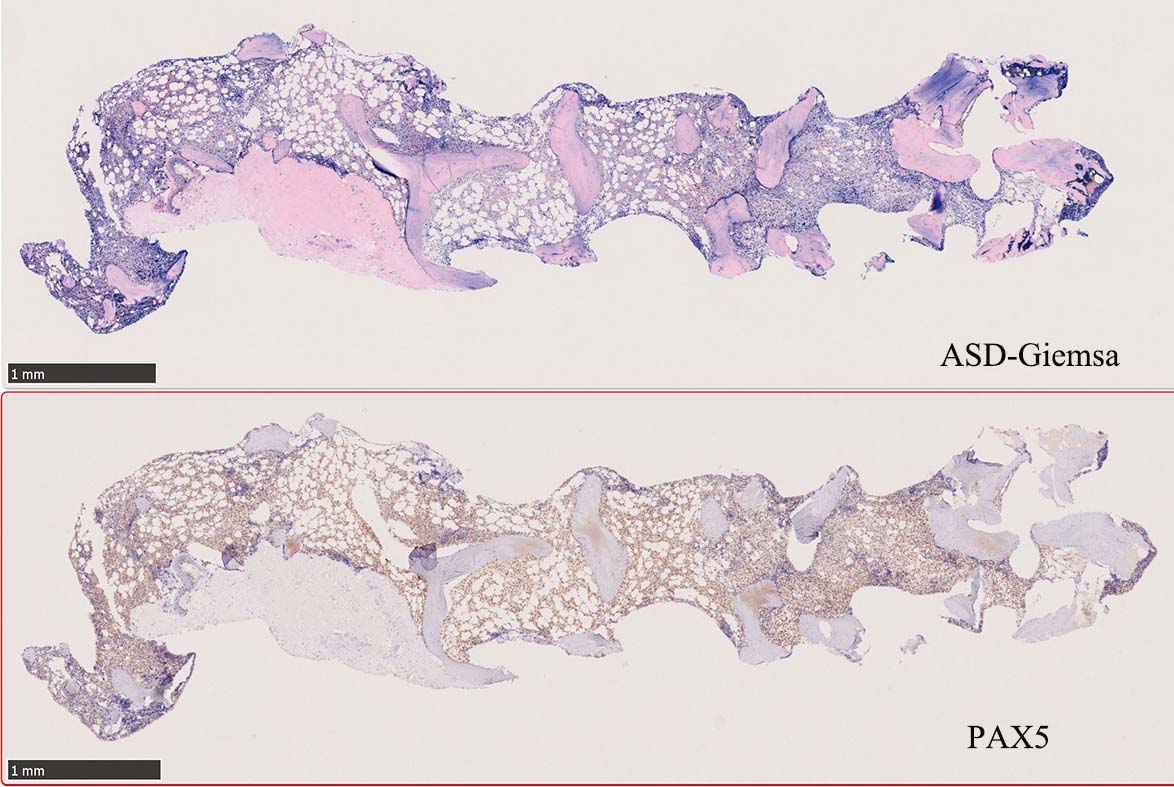

骨髄生検

bone marrow trephine biopsy: dry tapのため骨髄生検が行われる. cellularityは40-80%とhypercellular marrow. 流れのある細胞配列は線維化を疑わせる.

ASD-G 低倍率所見では赤芽球血島は幼若赤芽球の集簇巣が散在する, 顆粒球系細胞(ASDに赤く染色される)は減少,granulopoietic hypoplasiaを呈する.疎な集簇を示すmast cellsの増加がある.

ASD-G陰性の細胞がびまん性に増加しているように見える.

Hairy-FCM のコピー.jpg ASD-up-PAX5ok.jpg びまん性にPAX5陽性の小型B-cellsが増殖している.